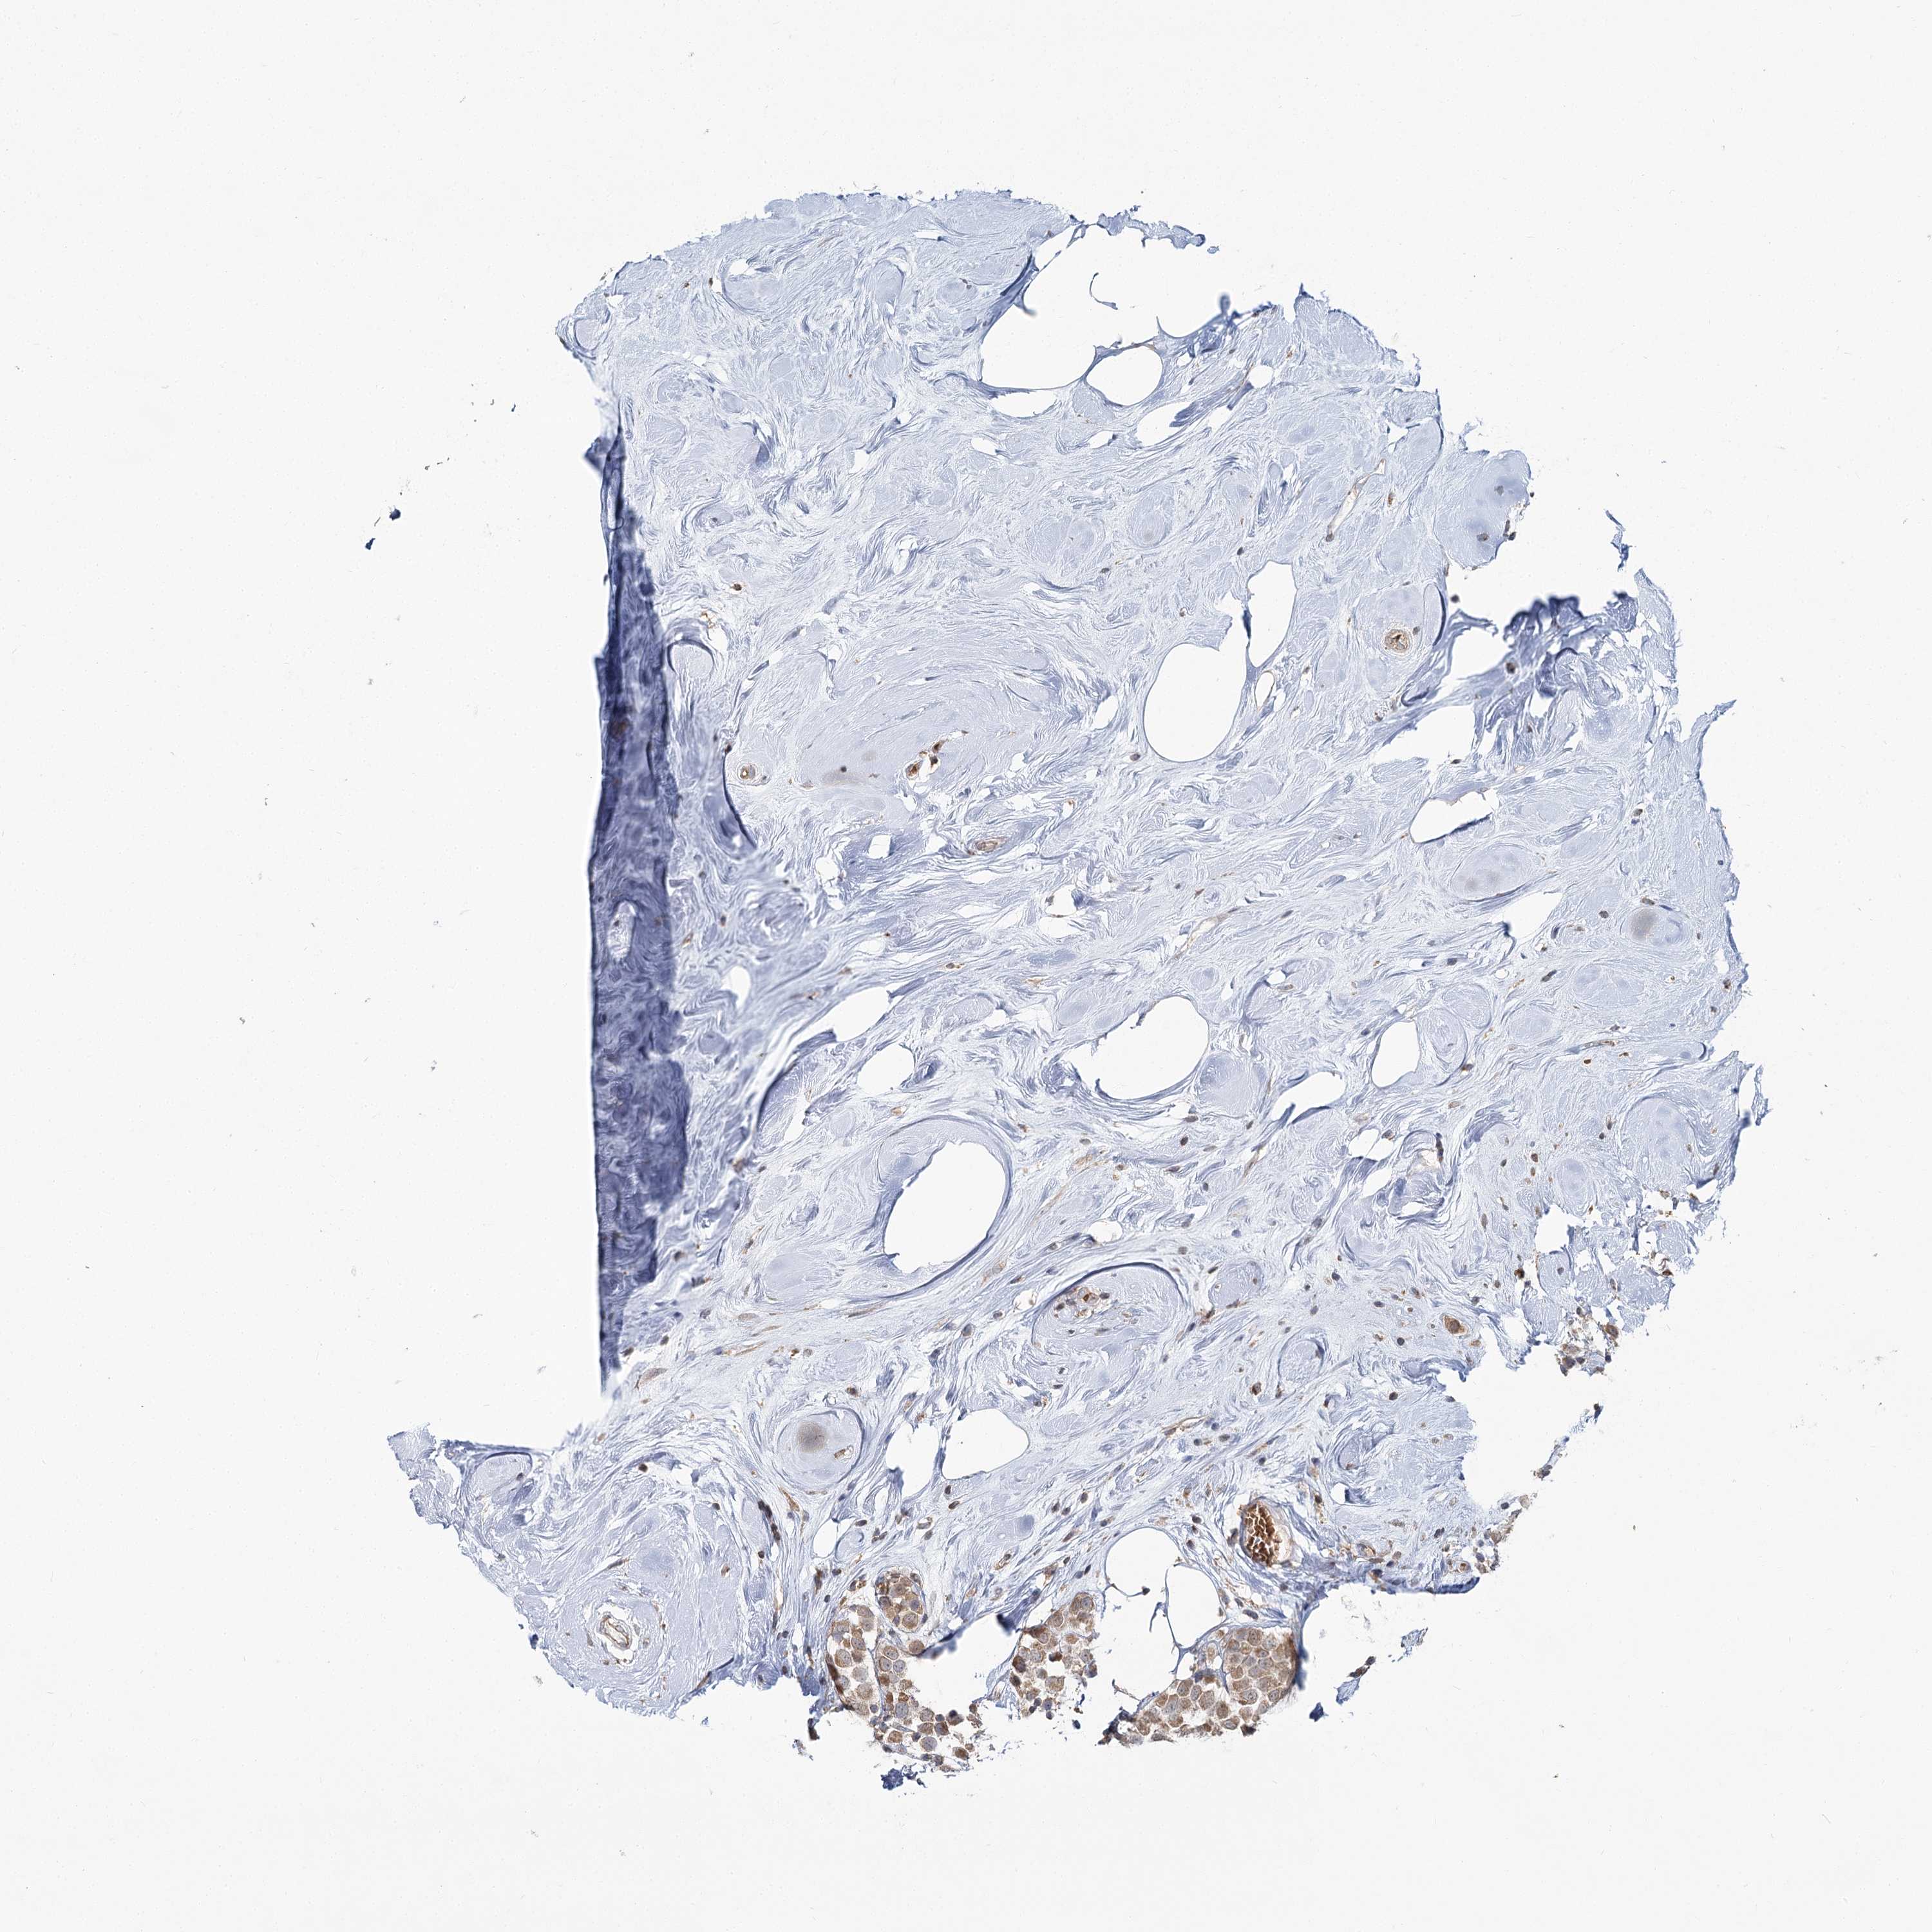

CANCER BREAST CANCER Show tissue menu

BRCA TCGA BRCA VALIDATION PROTEIN EXPRESSION